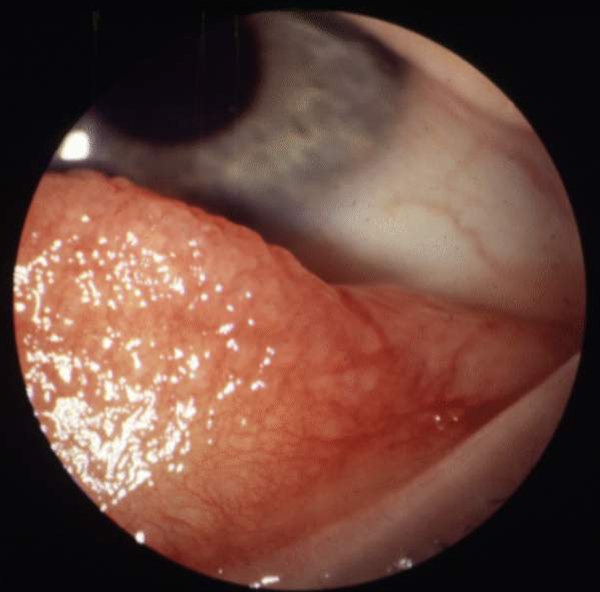

Urticaria starter med kløe og efter kort tid tilkommer kvadler i huden. Disse kan være af forskellig størrelse og ses som hvide eller lyserøde, eleverede, effloresenser.